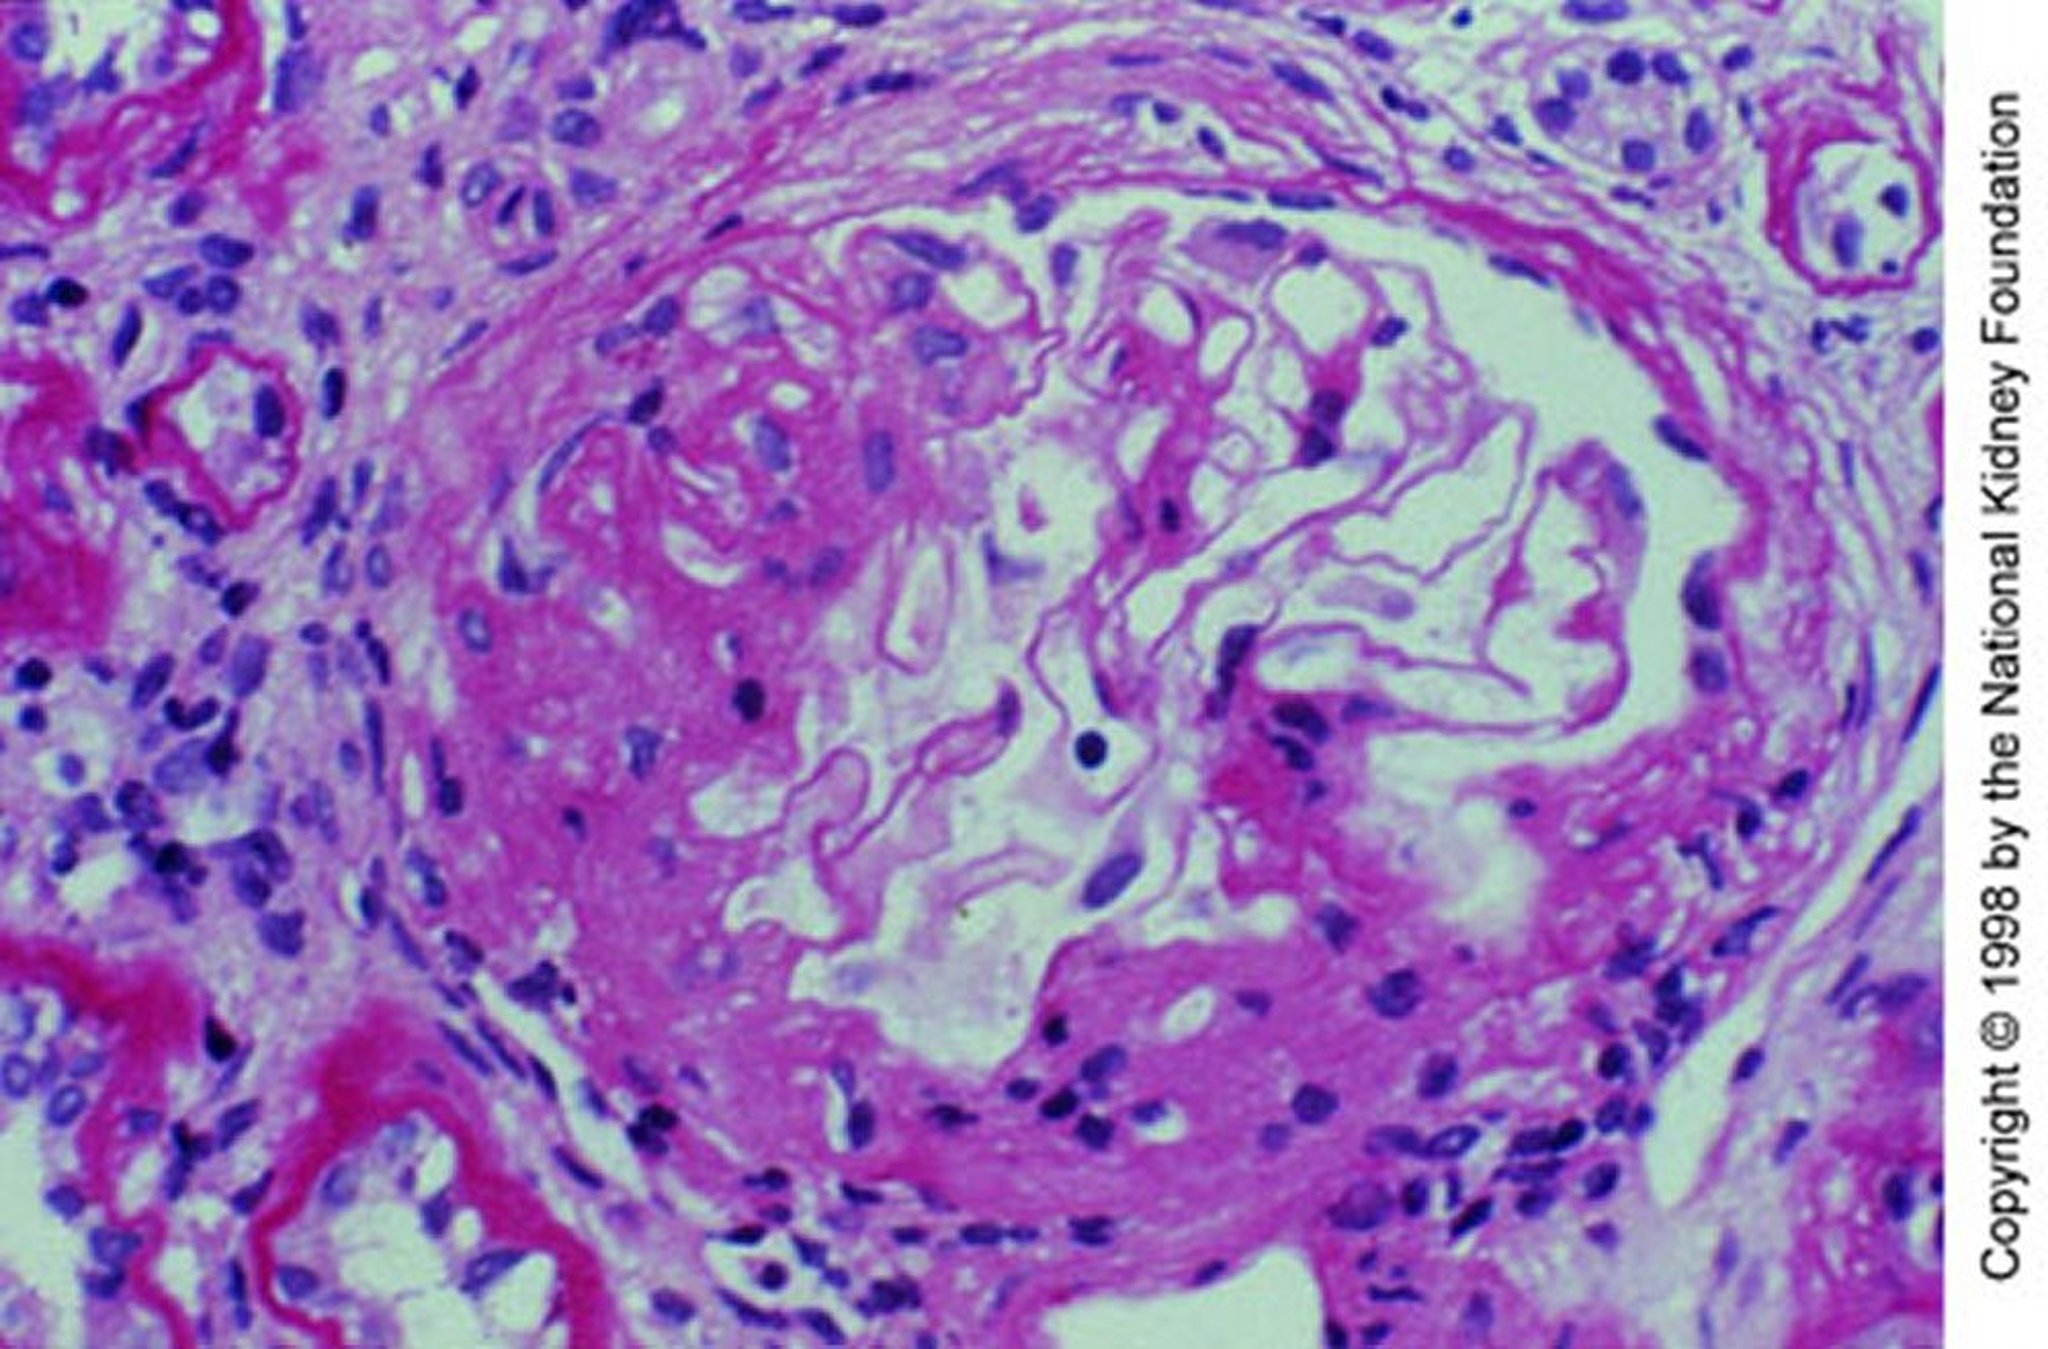

IgA-нефропатія (Мезангіальне поширення)

Mesangial expansion with segmental sclerosis (periodic acid-Schiff stain, ×200).

Image provided by Agnes Fogo, MD, and the American Journal of Kidney Diseases' Atlas of Renal Pathology (see www.ajkd.org).